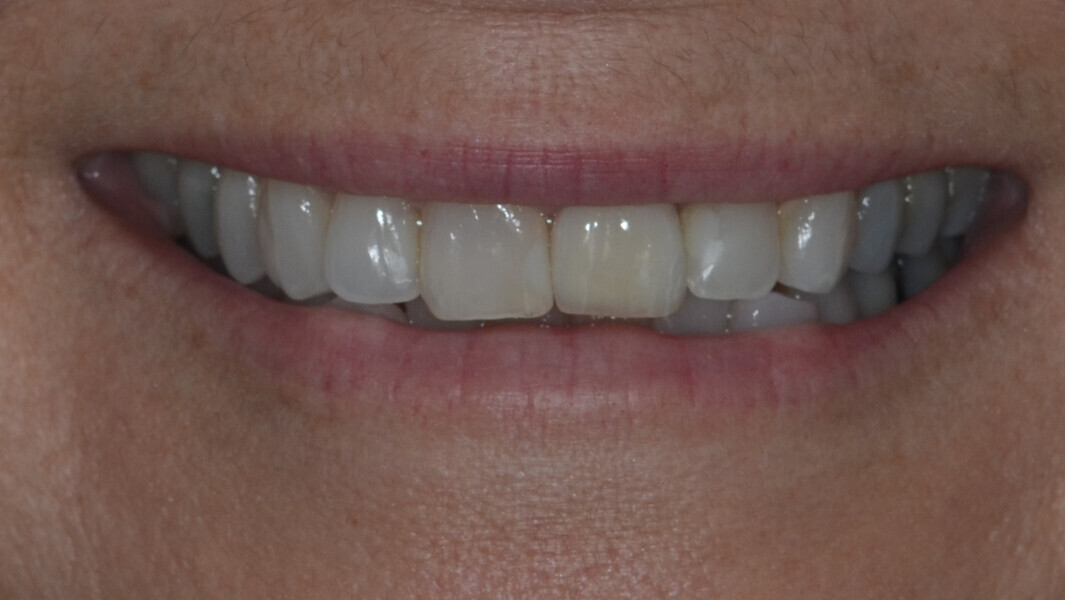

Fig. 31: Final result while smiling.